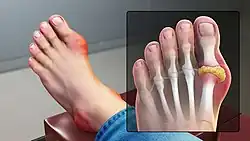

Gout can present in multiple ways, although the most common is a recurrent attack of acute inflammatory arthritis (a red, tender, hot, swollen joint).[7] The metatarsal-phalangeal joint at the base of the big toe is affected most often, accounting for half of cases.[10] Other joints, such as the heels, knees, wrists, and fingers, may also be affected.[7] Joint pain usually begins during the night and peaks within 24 hours of onset.[7] This is mainly due to lower body temperature.[4] Other symptoms may rarely occur along with the joint pain, including fatigue and a fever.[10][15]

Gout presenting as slight redness in the metatarsal–phalangeal joint of the big toe

Gout of the left MP joint of the big toe -